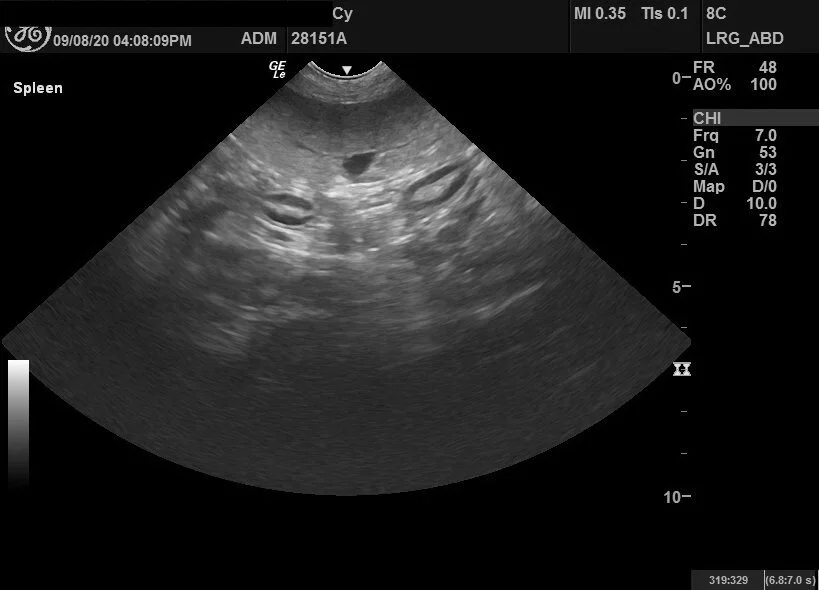

Uncomfortable with the initial wait-and-see plan, I opted to get a second opinion while also looking for someone who had an earlier availability for an ultrasound. I received a referral to a new office that takes walk-ins. Upon reviewing Cy’s initial labs, the veterinarian admitted him for a 72-hour IV treatment. These labs are following his hospitalization. During this visit, we also got an ultrasound.